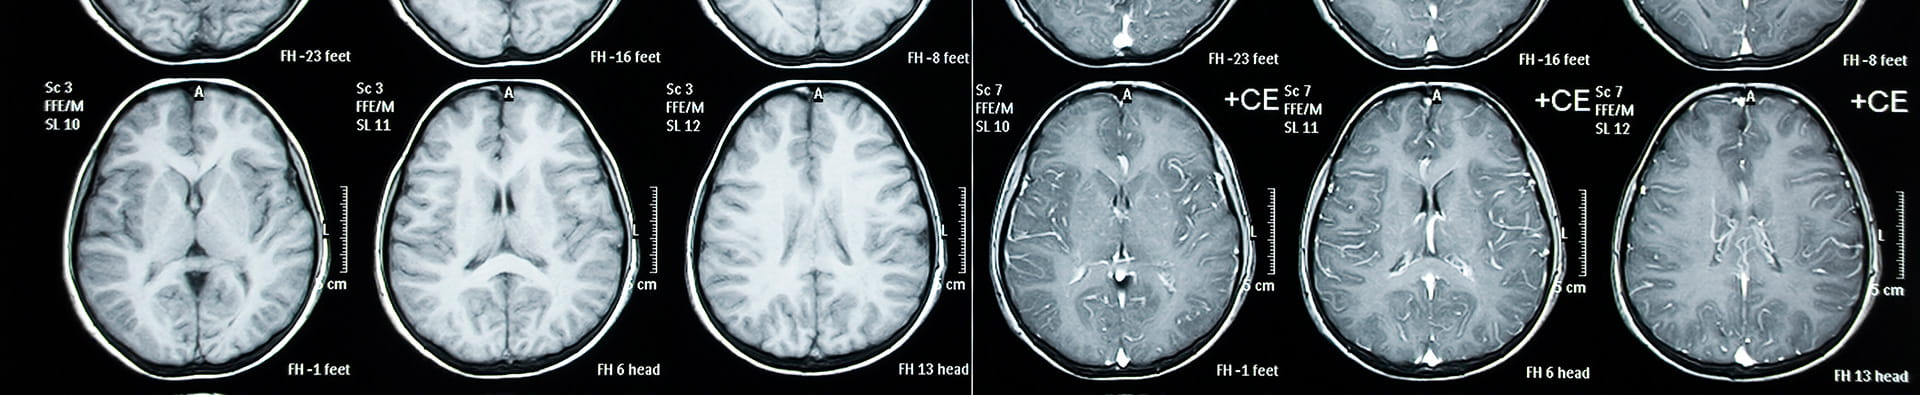

If your child has stomach pain, suffered a recent injury or illness, or has a mass that requires further examination, your doctor may suggest a CT scan (computed tomography, scan) also known as a CAT scan. CT scans create up-close digital images of organs, soft tissues, bones and blood vessels.

CT Scans are safe and painless, but they can still be scary to a child. Randall Children’s specialists are specially trained to care for infants, children and teens. You’ll have peace of mind knowing our pediatric radiologists and the Randall Care team provide the best possible experience for your child and use state-of-the-art software for enhanced images. The CT scan results help our specialists to make a thorough, timely diagnosis and, if necessary, a treatment plan for your child. Because safety is a top priority, our pediatric radiologists strive to expose young children to less radiation than adults.

First, assure your child that a CT scan is not scary, and that you will be close by throughout the whole process. Your child is given an injection of a color agent, and the contrast helps the provider see better. The contrast helps us to see blood filled organs helping us determine what is wrong and determine treatment. We will ask questions about allergies to make sure it is safe for your child. Contrast can make the child feel warm or flushed and make give them the urge to urinate (pee). These are normal and expected. This may feel warm or even sting, but the sensation will go away quickly.  As with all tests, you’ll be asked about any allergies to iodine, drugs, foods, or if your child has asthma. When your child is in the right position, a large machine will rotate around the table to take pictures. It’s important that your child lie very still during this process. The great news is that the procedure usually lasts no more than a couple of minutes.